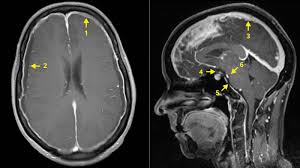

Die Lumbalpunktion LP ist ein invasives diagnostisches Verfahren aus dem Fachgebiet der Neurologie bei dem einem Patienten eine geringe Menge an Nervenwasser dem sogenannten Liquor cerebrospinalis entnommen und zur Analyse ins Labor geschickt wird. Das klingt erst einmal sehr gefährlich denn keiner möchte sich am Rücken oder dem Gehirn einer Untersuchung mit einer langen Hohlnadel unterziehen. Wenn die Lumbalpunktion so unangenehm oder schmerzhaft ist dass man das Gefühl hat dass es nicht mehr geht unterbricht man den Vorgang.

Je nach Krankheitsbild und Therapiebedarf wird die Hirnwasser-Untersuchung auch bei einem stationären Klinikaufenthalt durchgeführt. Antworten Antje 28052008 1717. In den vergangenen Jahrzehnten wurden LP aufgrund befürchteter postpunktioneller Beschwerden oder Komplikationen nur selten ambulant durchgeführt. Außen liegt die harte Hirnhaut nach innen schließt sich weiche Hirnhaut an. Dazwischen liegt ein schmaler Spalt der sogenannte Subarachnoidalraum in dem sich das. Ich bin ins KH da musst du aber keine 3 Tage bleiben. Bei mir wollte der Neuro das nur ambulant machen. Eine Verschnaufpause oder auch ein Verschieben der Punktion auf den nächsten Tag darf sich jeder einfordern. Nach der Hirnwasser-Entnahme ist je nach Verlauf eine Ruhezeit von vier bis 24 Stunden nötig.